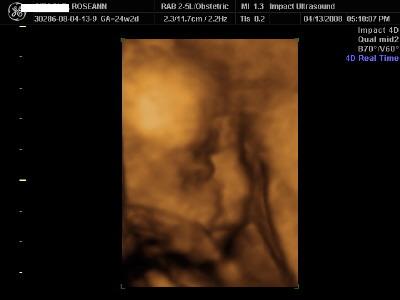

Here are 3D pics of Seamus Finn I was a little over 24 weeks when I had them done yesterday. i went to Impact Technologies in East Meadow. They were great. We bought all the grandparents and they got to sit on couches and they projected the sonogram on a big movie screen on the wall! We went out to dinner afterwards and our parents surprised us and told us they are buying all 4 pieces of our furniture!! We are very excited

The first pic is my absolute favorite. He didnt want to be bothered much. He kept turning his @ss to us and we had to jiggle my belly to get him to flip!! And the tech said that he definately has hair! He showed us in 1 of the pics the squiggly lines! Image Attachment(s):

That is incredible! I love the details of the face and the one of him yawning.